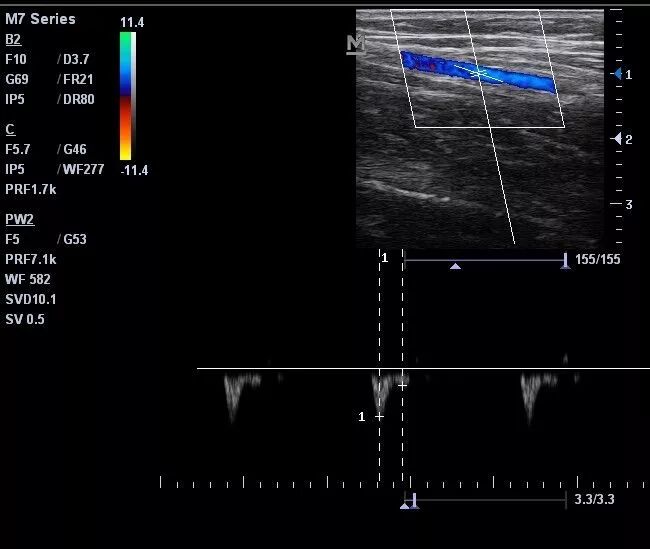

下图中,取样容积很小,血流频谱的宽度较小,结果容易偏高。

什么是超声容积探头血流量测定 |取样容积和角度θ_https://www.jmylbn.com_新闻资讯_第4张